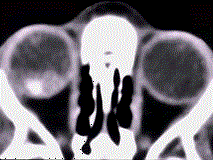

男,3岁,家长发现右眼瞳孔发白3个月(如图),眼眶CT如图,对该病描述错误的是 ( ) A、90%发生于3岁以前B、男性多于女性C...

问题 男,3岁,家长发现右眼瞳孔发白3个月(如图),眼眶CT如图,对该病描述错误的是 ( )

选项 A、90%发生于3岁以前 B、男性多于女性 C、可出现钙化灶 D、是儿童最常见的原发性眼内恶性肿瘤 E、双眼发病约占30%~35%

答案 B